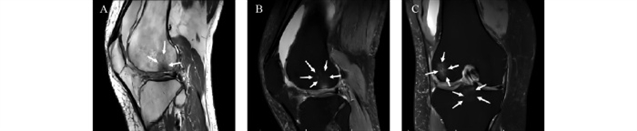

骨关节炎进展中,软骨下骨经历了一系列的特征性病理变化。首先是早期微损伤:机械应力异常导致骨重建失衡,成骨细胞与破骨细胞无法协同工作。破骨细胞过度活化会使骨板变薄、孔隙率增加,骨小梁密度降低、结构破坏,出现微骨折,此阶段在磁共振成像(MRI)上可观察到软骨下骨微骨折的低信号表现(图1)。此阶段软骨形态学改变尚不明显,但软骨基质中蛋白聚糖减少,炎症因子和基质金属蛋白酶水平已显著升高。微损伤进一步发展为骨髓水肿样病变(SBMLs),表现为骨髓纤维化、血管异常和局部脂肪坏死,是骨关节炎进展的重要影像学标志,在磁共振T2加权脂肪抑制序列中呈现高信号区域(图2)。骨髓水肿样病变通过增加骨-软骨间物质交换通道,促进炎症因子和破骨细胞前体侵入软骨,加速软骨降解,并与骨关节炎疼痛密切相关。长期异常力学刺激下,骨髓水肿区域逐渐形成软骨下囊肿(SBCs),其内含血管、神经纤维和炎症因子,在磁共振T1加权像中表现为低信号囊性结构,周围伴骨髓水肿(图3)。晚期则出现软骨下骨硬化,骨小梁增厚、排列紊乱,导致关节应力分布异常,加剧软骨损伤。

图1 65岁女性膝关节骨关节炎的磁共振成像。(A)矢状位T1加权像显示股骨远端轻微软骨下骨塌陷,软骨下骨微骨折呈低信号(白色箭头)。(B)矢状位T2加权脂肪抑制像显示股骨远端同一病灶(白色箭头)

图2 62岁女性膝关节骨关节炎的磁共振成像。(A)矢状位T1加权像显示股骨远端弥漫性骨髓水肿,呈低信号(白色箭头)。(B)矢状位T2加权中间加权脂肪抑制像显示股骨远端同一病灶(白色箭头)。(C)冠状位脂肪抑制质子密度(PD)MRI显示股骨内侧髁负重区及胫骨前交叉韧带止点下方骨髓水肿(白色箭头)